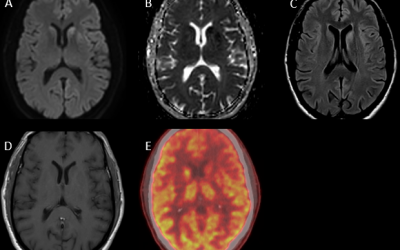

Caso del mes Abril 2026

« Todos los casosAutores Adrián Marín Rodríguez, Gonzala Fernández de Troya, Carmen González Soto....